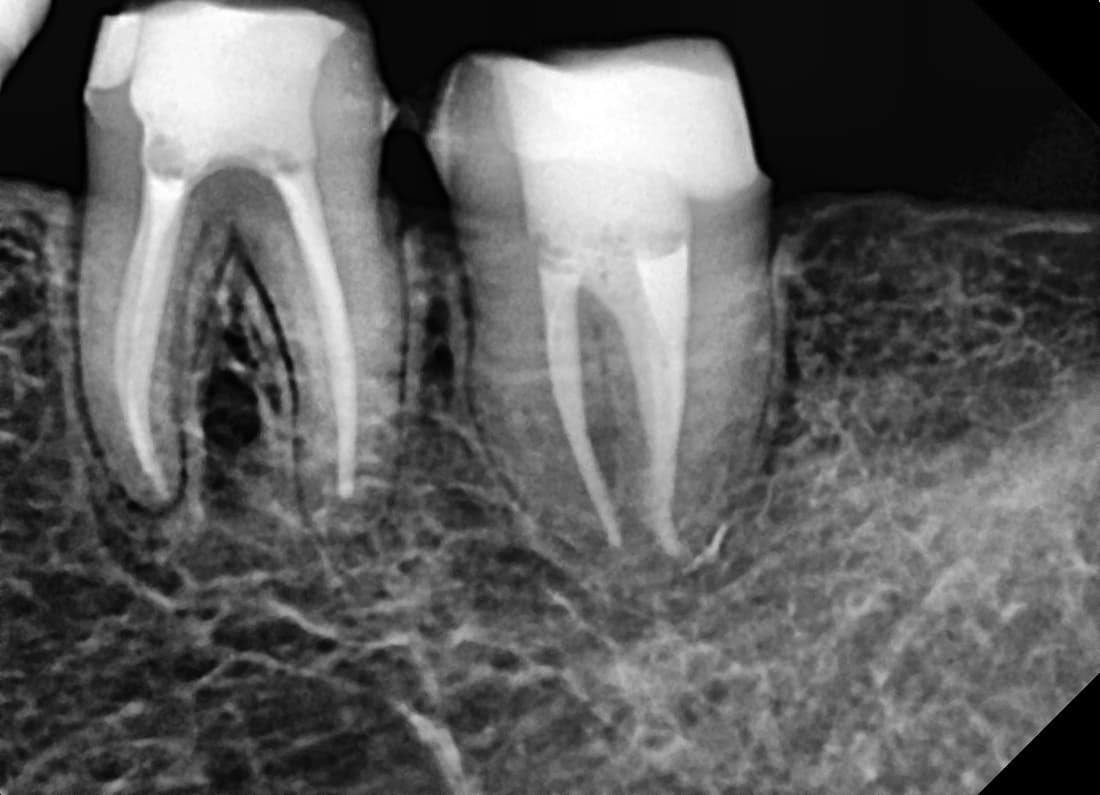

Periapical Lesion Healed

Molar recommended for extraction due to root inflammation

Before

After

Complete healing of periapical lesion 1 year 2 months after root canal